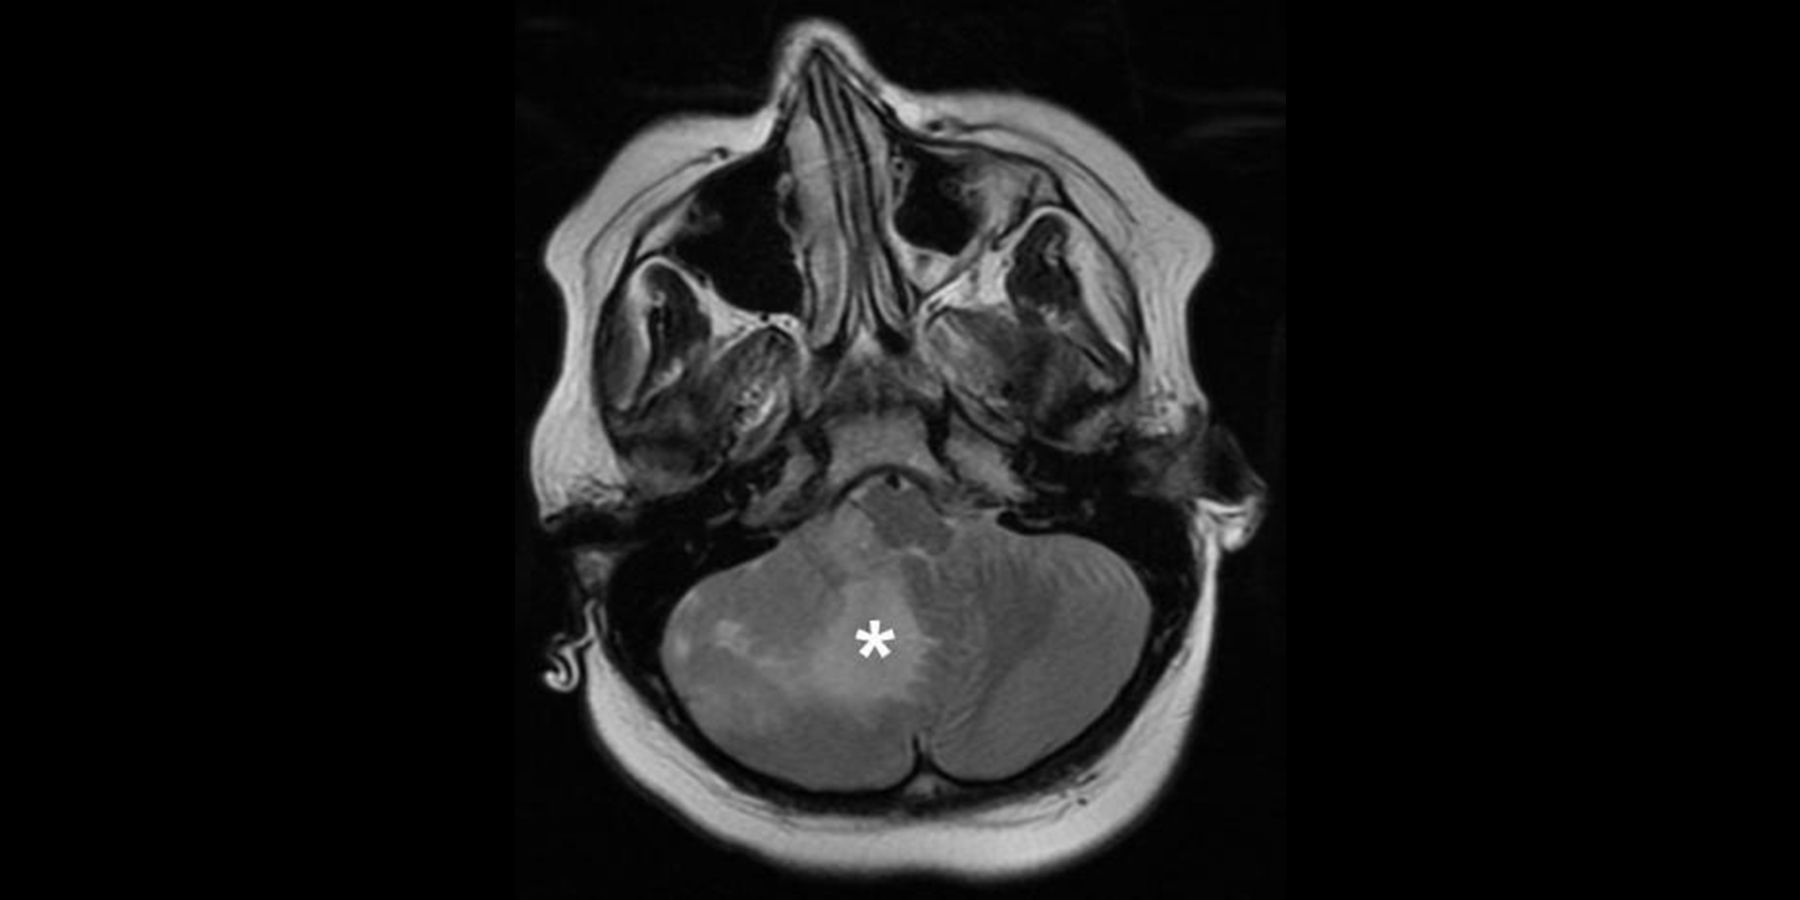

Scientists at Sanford Burnham Prebys Medical Discovery Institute, University of California San Diego School of Medicine and Hopp Children's Cancer Center Heidelberg (KiTZ) have demonstrated that personalized drug screens can be used to identify new therapeutic candidates for medulloblastoma, the most common malignant brain cancer in children.

Efforts to find personalized treatments for medulloblastoma, which comprises four distinct subgroups—WNT, Sonic hedgehog (SHH), Group 3, and Group 4—have not been successful to date. Most patients still receive the same treatments—brain surgery to remove the tumor followed by radiation and chemotherapy—in spite of the different molecular characteristics of the tumors. As a result, one-third of children succumb to the cancer; and the children who do survive often have severe, lifelong side effects from the treatment, including cognitive impairment and a greater likelihood of developing cancer again.